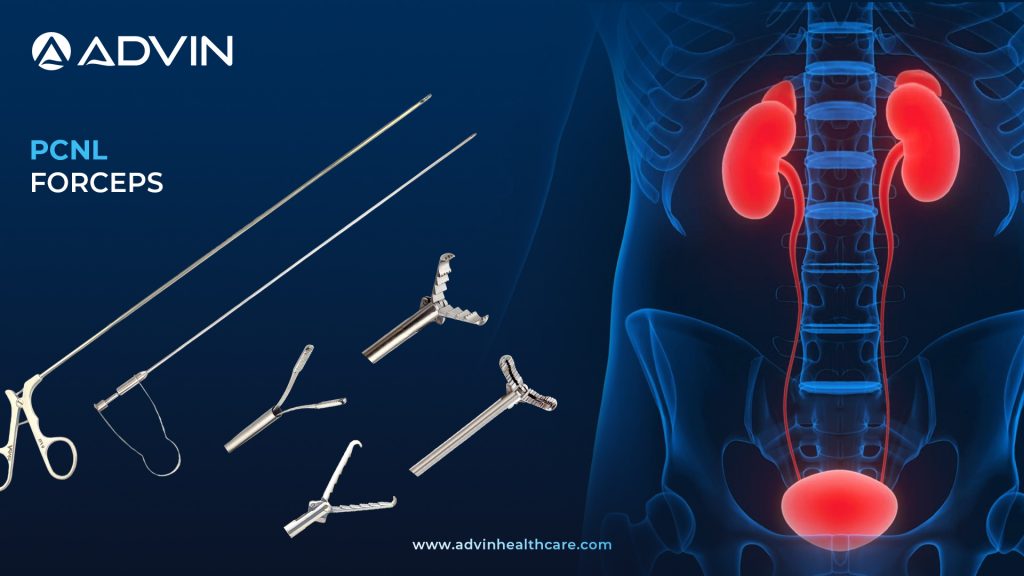

PCNL Forceps – Enhancing Stone Grasping in Percutaneous Procedures

Introduction to PCNL Forceps: Precision Retrieval Tools for Renal Stone Surgery PCNL Forceps are specialized instruments used during Percutaneous Nephrolithotomy (PCNL) to grasp and remove kidney stones. These forceps are inserted through a nephroscope to access and extract calculi directly from the renal pelvis. They are available in various jaw...